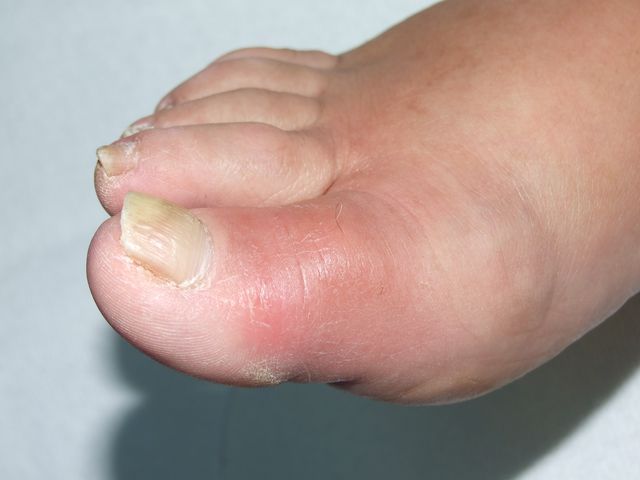

Podagra gotosa.